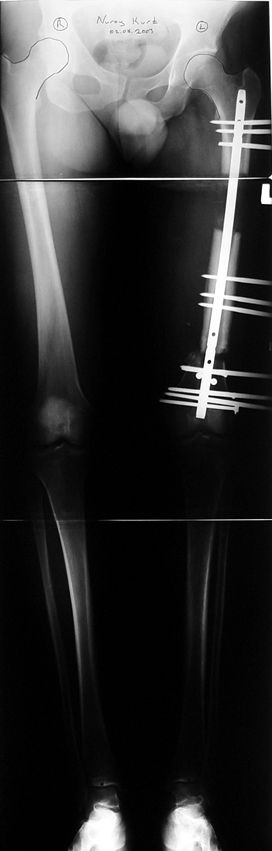

Vaka 2